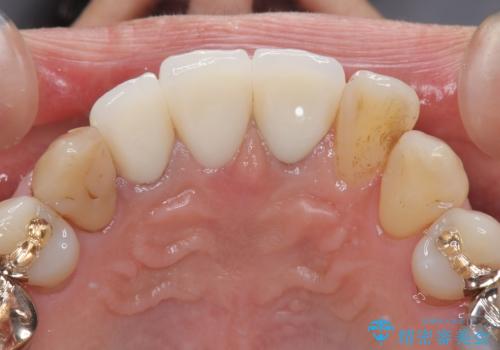

- 昔入れた前歯を綺麗にしたいことを主訴に来院された患者様です。

根尖に病変を認めたため、根管治療を行いセラミッククラウンにて修復を行なっています。

根管充填はMTAにて行なっています。